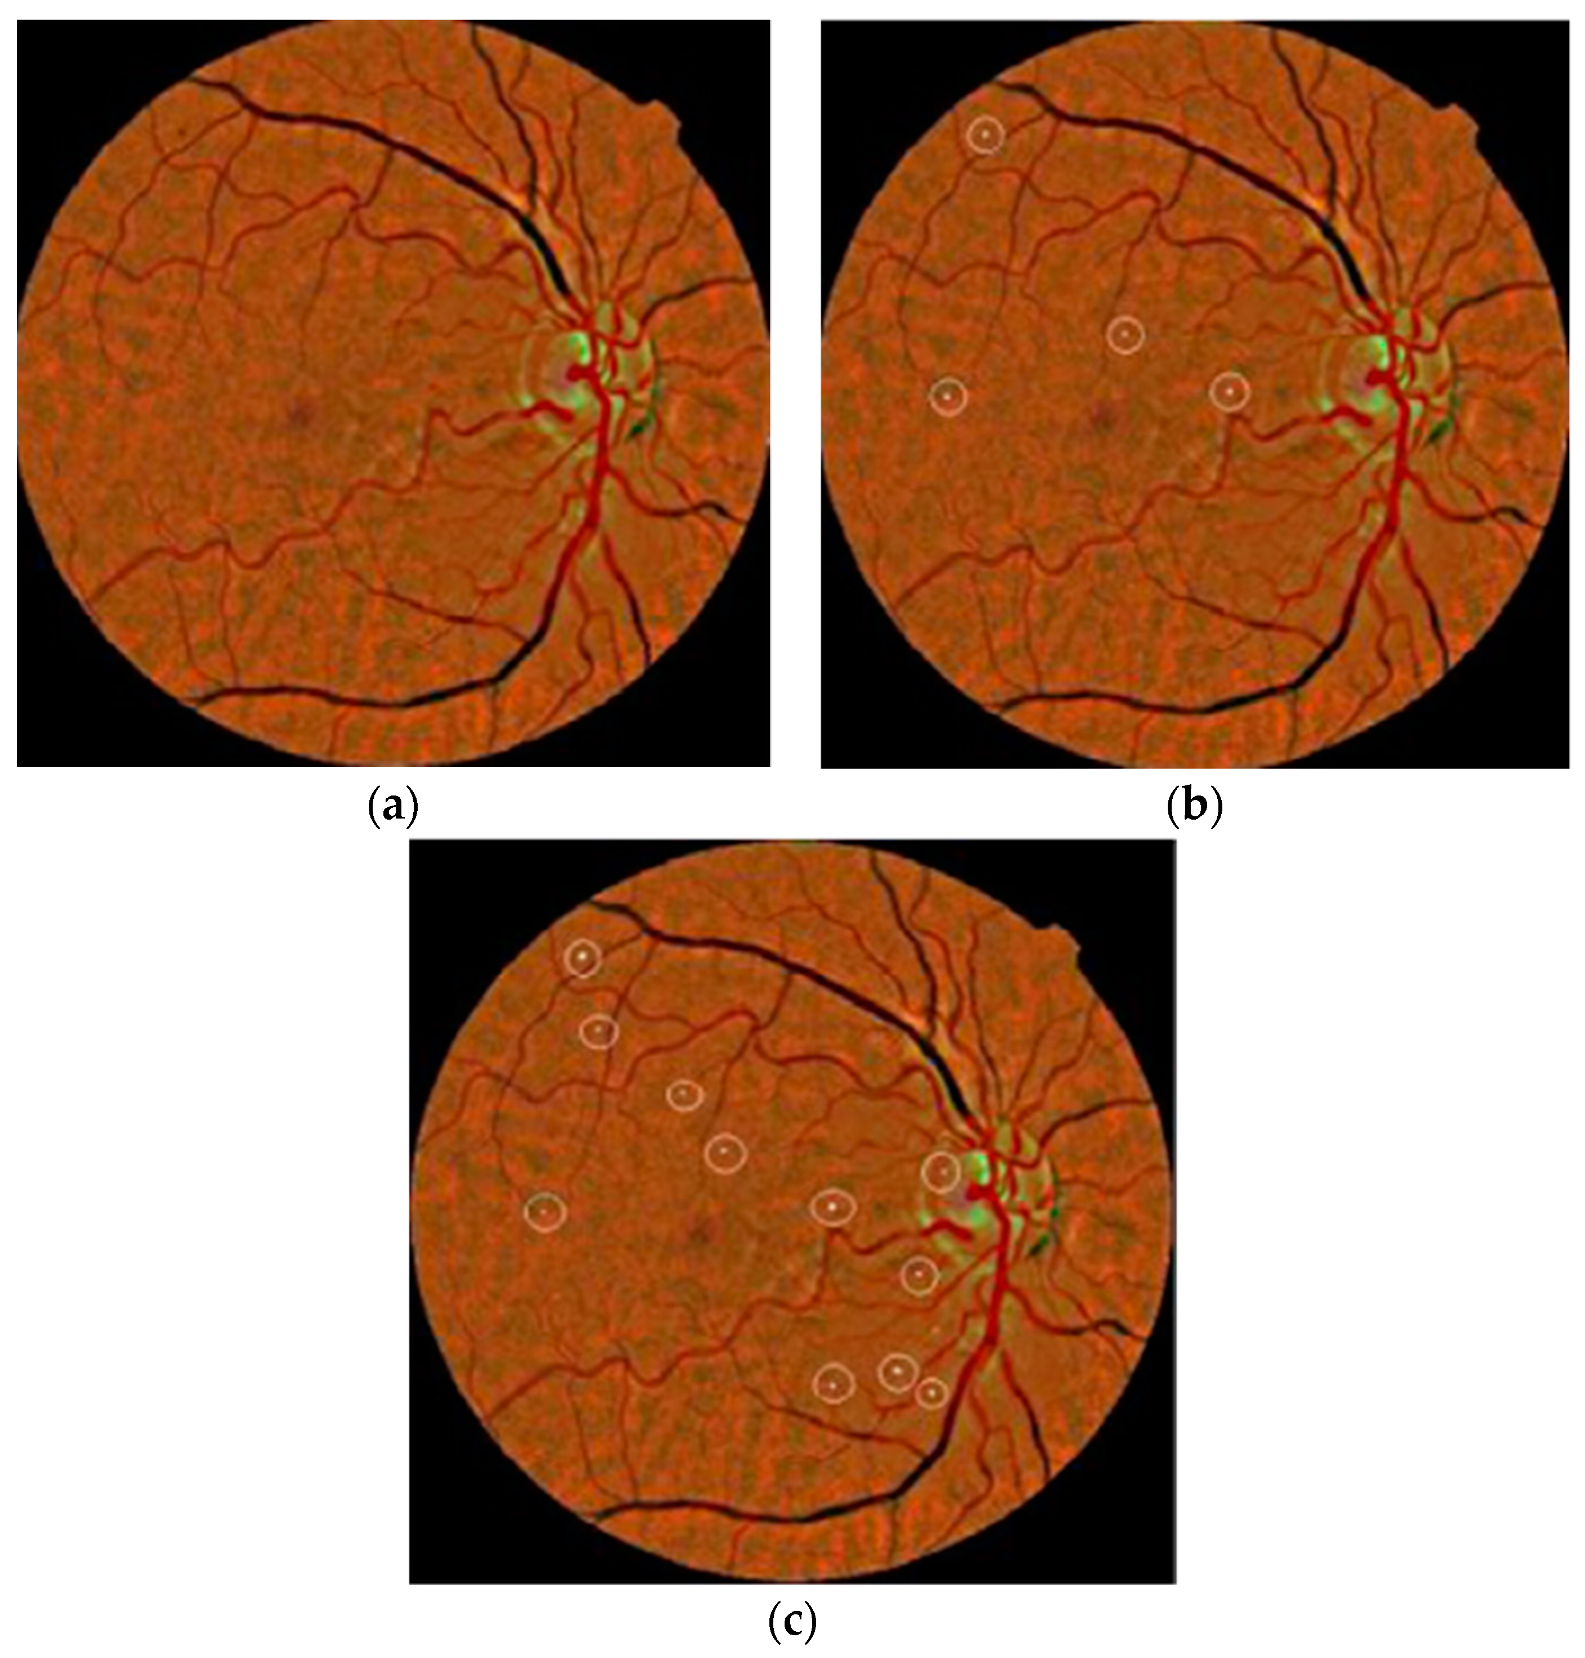

The authors in [74] considered a coarse segmentation method to initially localize the MA candidate region. Further, a naïve Bayes classifier was applied to extracted MA pixels and discriminated true MA points from non-MA points, yielding a classification accuracy of 99.99% and an SE of 82.64%. However, their classifier, i.e., naïve Bayes, was computationally expensive during training and was also limited on faint and blur MA pixels. To solve this problem, a contrast limited adaptive histogram equalization (CLAHE) technique was implemented in [75] to detect poor contrast and blurry MA pixels. They divided input images into small and contextual tiles in order to detect tiny and low contrast MA pixels. They obtained an SE of 85.68%. However, their approach was only tested on 47 images, which limits its generalizability to other medical ailments. A sparse representation classifier (SRC) was applied in [76] followed by dictionary learning (DL) to detect MA pixels. Initially, a Gaussian correlation filter was incorporated to localize the MA region. Further, those MA features were given to the SRC to classify true MA points from non-MA pixels. The authors achieved an SE of a 0.8% increase rate. However, their proposed dictionaries were generated artificially, thus lacking discriminative power in MA detection. Akram et al. in [77] implemented a system to grade whether retina images belong to MA or non-MA regions. The authors obtained an accuracy of 99.40%. However, the method was computationally expensive, but presented better features for improving the discriminative performance of the classifier. In that line, sparse principal component analysis (SPCA) and ensemble-based adaptive over-sampling approaches also reduced false positives in MA detection and eliminated the class imbalance problem in color fundus images with an average 0.90 AUC score [78,79]. Javidi et al. in [80] considered morphological analysis and two dictionaries for MA detection using fundus images. The MA candidate region was initially localized using the morelet-based wavelet algorithm. The MA extracted features were then evaluated by binary dictionaries to classify the true MA region from non-MA pixels. The authors obtained an ROC of 0.267. Their proposed MA detection results are shown in Figure 6.

Figure 6.

(a) Input image; (b) manual annotated MAs; (c) proposed MA detection by [80].

Nevertheless, the method was expensive in terms of the execution time and was unable to detect MA pixels on faint and poor contrast images. A deep learning strategy called stacked sparse auto encoder (SSAE) was applied by Shan et al. in [81] for MA detection. Initially, images were cropped into small patches. These patches were then processed by the SSAE model to learn high-level features from patches. Finally, a soft max classifier was used in the output layer to give a patch probability of being a true MA or false MA. They reported an AUC of 96.2%. Another study in [82] proposed a two-layer approach called multiple kernel filtering for MA and HM segmentation. Small patches were used instead of the whole image to deal with the varied size of lesions, and finally, a support vector machine (SVM) was applied on selected candidates to distinguish true MA and HM patterns from other parts of an image. They achieved an AUC of 0.97. Adal et al. in [83] presented a machine learning algorithm for MA detection. Input image was first normalized and then different scale-based descriptors were applied for feature extraction. Finally, a semi-supervised algorithm was trained on the extracted candidate features to classify MA points from non-MA intensities, obtaining an AUC of 0.36. The methods in [81,82,83] were found to be unable to address the over fitting problem for much larger datasets and contained low discriminative power. A summary of MA detection methods is given in Table 4. It describes the respective methods with their utilized dataset and size.